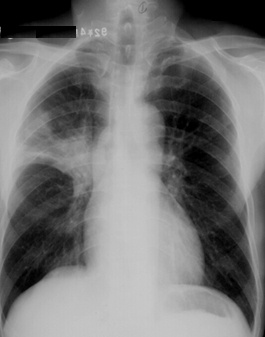

满肺可见“满天星”,根据公式诊断肺转移瘤

斑片状阴影位于双肺尖,根据公式诊断浸润性肺结核